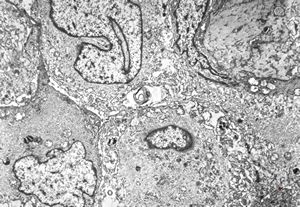

normal seromucinous salivary gland